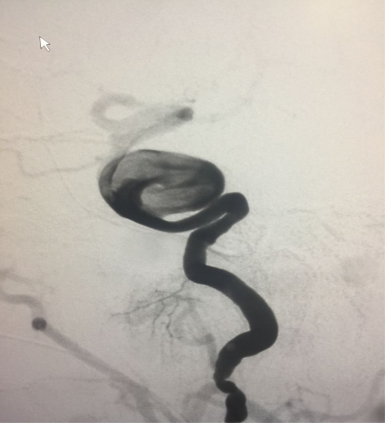

进一步填塞,但可以看到下方支架打开不满意

帯毛圈也填了,“子弹”打光后(密网支架十5个圈)最后造影

最后应用J型导丝及球囊将下方支架充分打开并贴壁,正位片所见